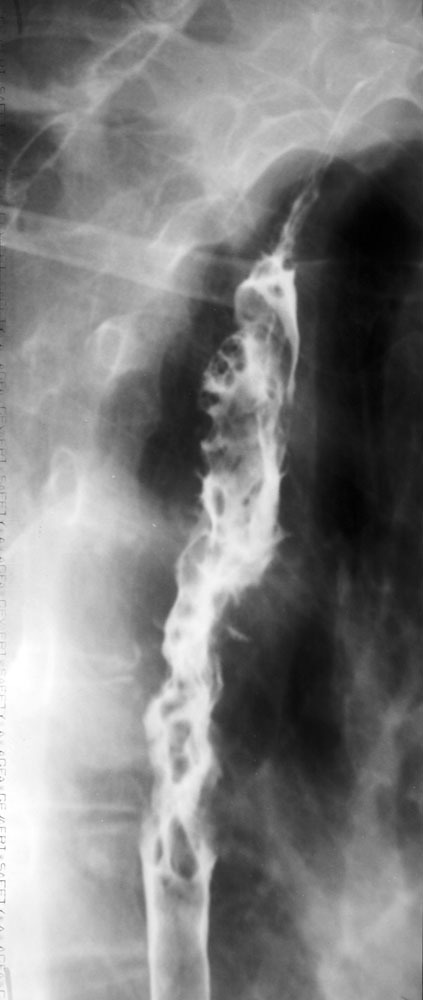

What kind of investigation is this?

What does the image show?

Barium swallow.

Extensive ulcerating oesophageal carcinoma